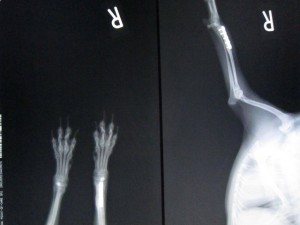

パピヨン ♀ 8か月 2.1kg

さくを飛び越えたときにキャンと鳴いて右前足を痛がっているとのことで来院。レントゲンにより、右橈尺骨遠位端骨折を確認した。

術前のレントゲンです。

右前肢橈尺骨遠位端骨折です。